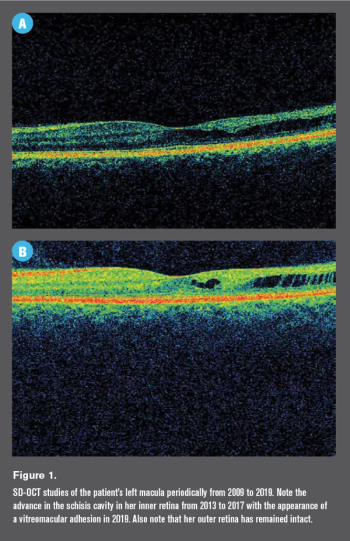

Retinoschisis can make diagnosing open-angle glaucoma especially difficult for optometrists.